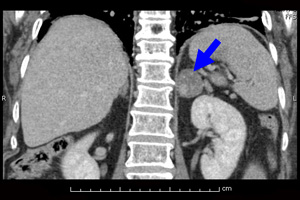

대학병원 전공의 시절 우울증으로 입원한 젊은 환자가 있었다. 치료가 잘 안되고 입원이 장기화되는 와중에 다른 문제로 찍은 복부 영상검사에서 희귀한 내분비 병변이 우연히 발견되었다. 의료진과 가족은 모두 흥분했다. 우울증을 일으키게 한 명백한 원인을 말 그대로 기적 같이 발견한 것이었다. 그렇다면 수술로 문제의 호르몬을 분비하는 병변만 제거해주기만 하면 우울증이 완치되는 상황이었다.